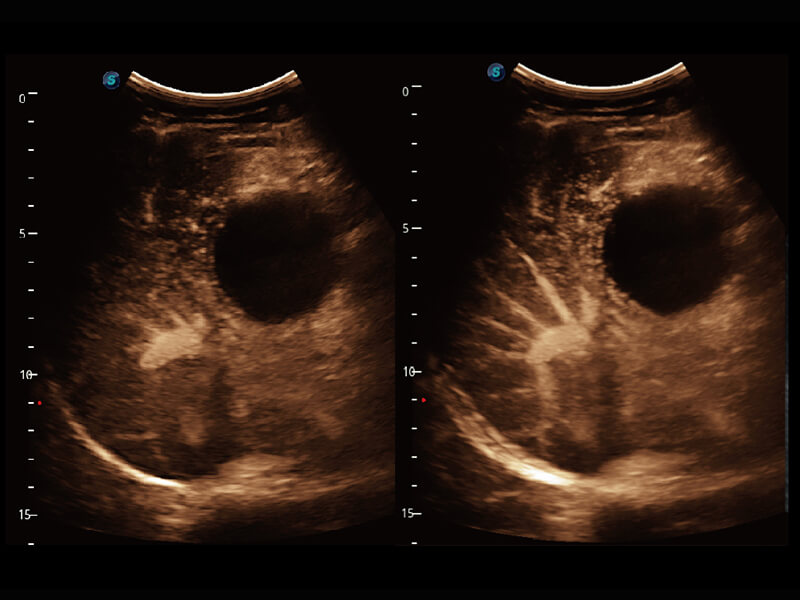

S60探头工艺,从前端信号处理每一个环节采集无损声学数据,真实还原组织原貌,再现解剖细节。

• 腹部单晶体探头( C1-6A )

高分辨率容积成像 栩栩如生

超宽频带技术,为容积成像带来优质的二维图像基础,为您呈现丰富的结构细节,栩栩如生地展示宝宝的宫内形态以及各种组织的立体结构。